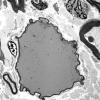

Giant Axonal Neuropathy (GAN) (3)